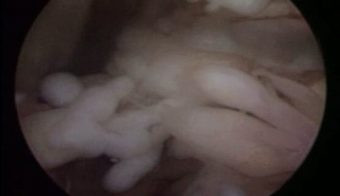

Artroscopia de Rodilla Sinovitis Lipoma Arborescens

Envíado por Dr. Luis Rodolfo Morales Choto